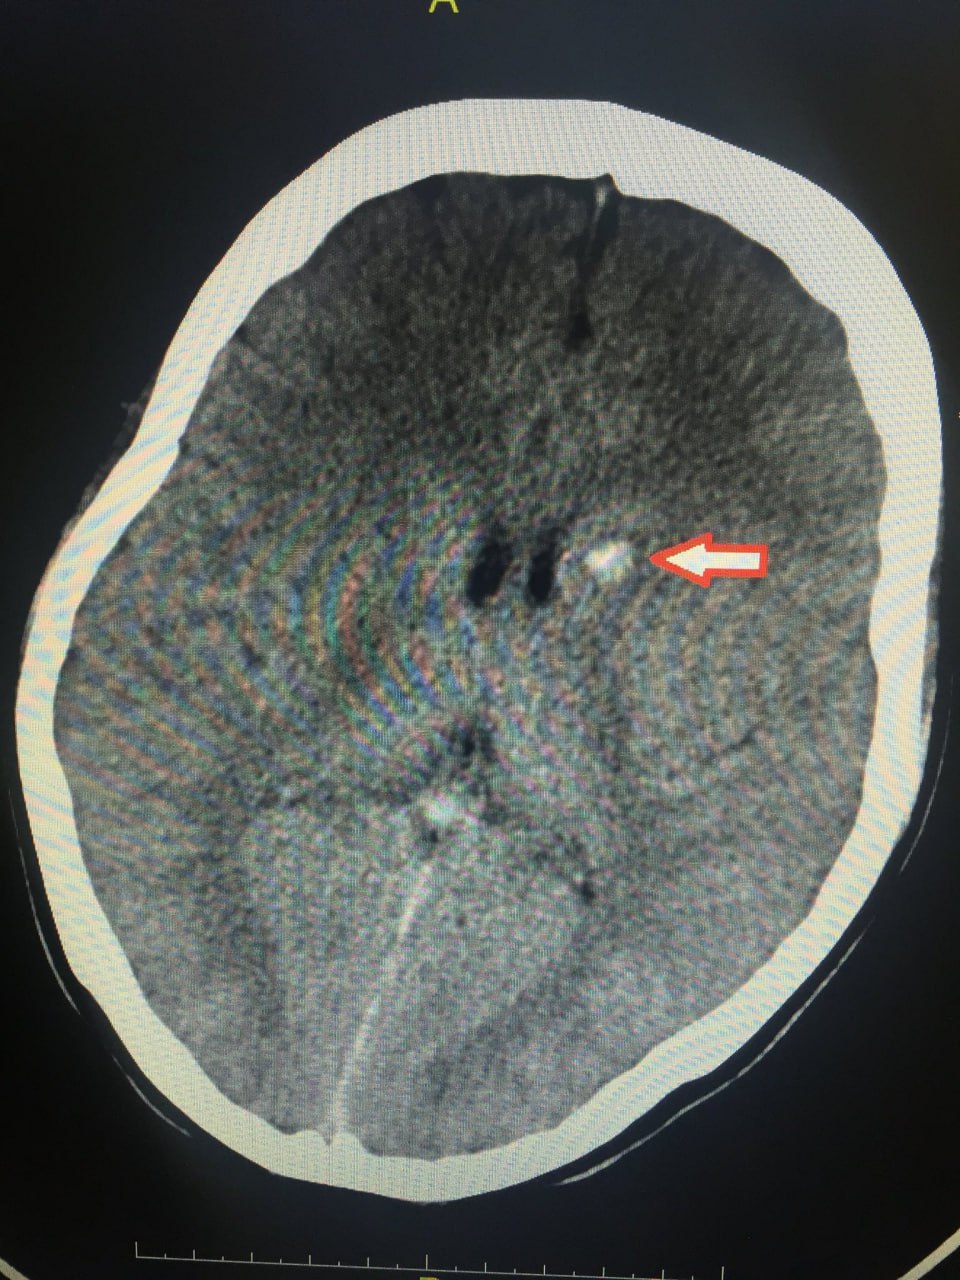

PGS Huy Thắng nhắc lại trường hợp đầu tiên vào năm 2016, một bệnh nhân nữ, còn rất trẻ (sinh năm 1994) nhập viện BV Nhân dân 115 vì yếu tay chân Phải và mù mắt Trái, ngay sau khi bị tiêm thẳng chất làm đầy vào vùng cạnh mũi.

Khi khảo sát MRI não, cho thấy hình ảnh khá ấn tượng với một chuỗi rất nhiều emboli gây tắc nhiều mạch máu nhỏ tại vùng giáp ranh bán cầu Trái. Sau đó gây chuyển dạng xuất huyết não.

Một số các phân tử có kích thước nhỏ hơn sẽ tiếp tục di chuyển về động mạch mắt (nhưng không gây thuyên tắc động mạch mắt, do các phân tử này có kích thước nhỏ hơn) qua động mạch cảnh trong bên trái vào gây thuyên tắc tại các động mạch vùng vỏ não tận cùng.

Sau khi gây thuyên tắc, các phân tử acid hyaluronic có thể gây viêm mạch máu tại chỗ và gây xuất huyết não thứ phát sau đó.